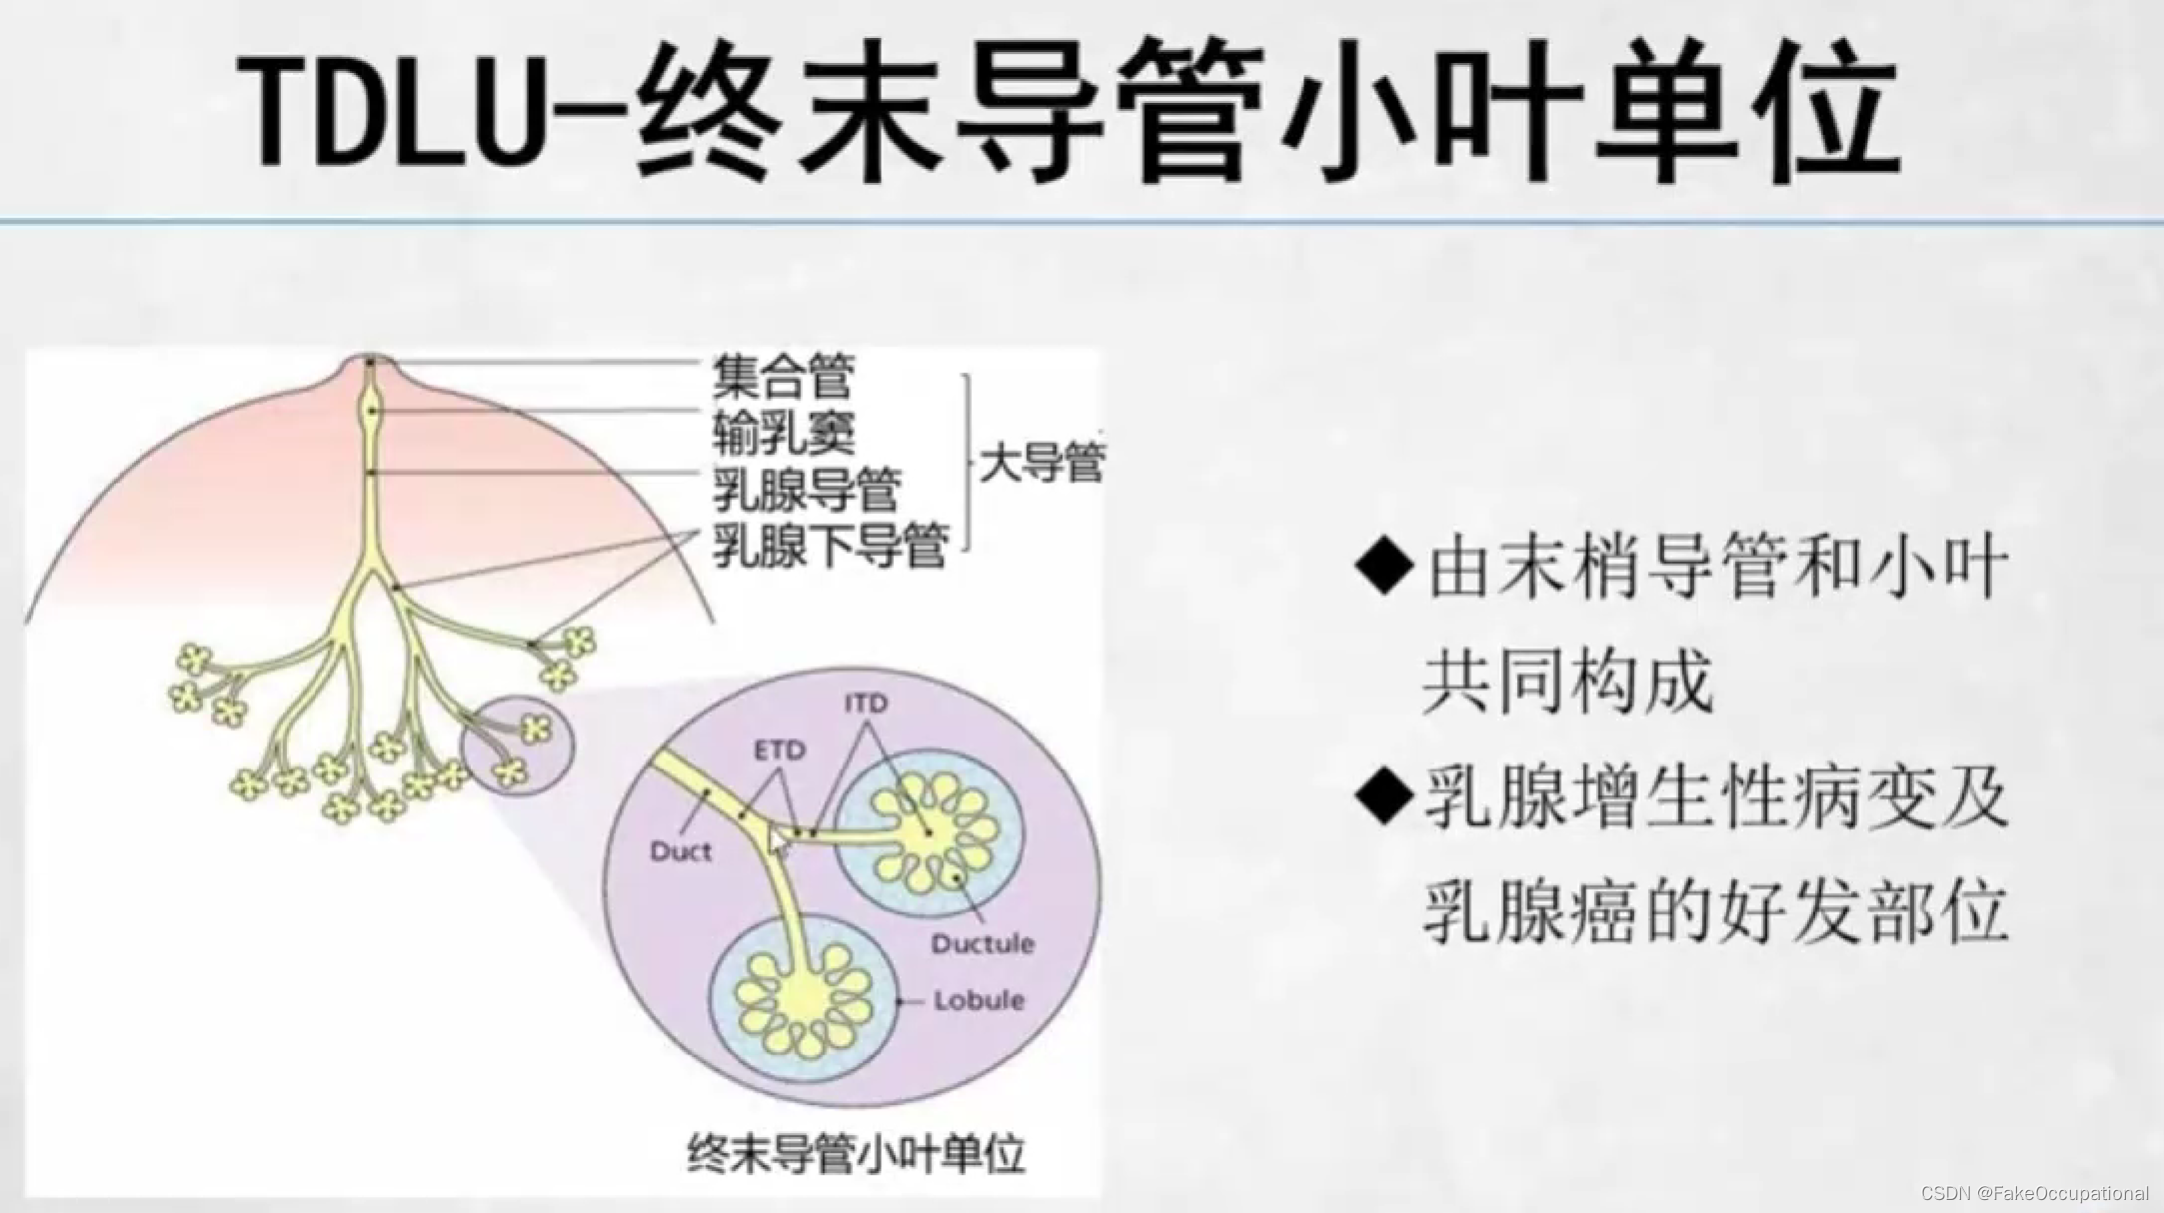

乳腺的生理解剖概要

乳腺的生理解剖概要